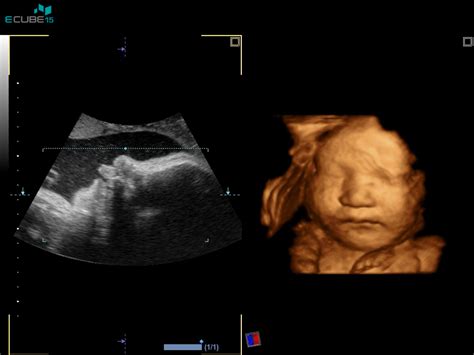

Nuhalna svetlina (NS): Ta ultrazvočni pregled se izvaja med 11. in 14. tednom nosečnosti. Meri se količina tekočine v podkožju vratu ploda. Povečana nuhalna svetlina je lahko znak kromosomske nepravilnosti, vključno z Downovim sindromom. Pregled je neškodljiv za plod in traja približno 15 minut. Za pravilno izvedbo in interpretacijo je ključno, da ga izvaja ginekolog z mednarodno licenco Fetal Medicine Foundation (FMF). Poleg nuhalne svetline se pri tem pregledu ocenjuje tudi prisotnost nosne kosti, ki je pri plodovih z Downovim sindromom pogosto odsotna.